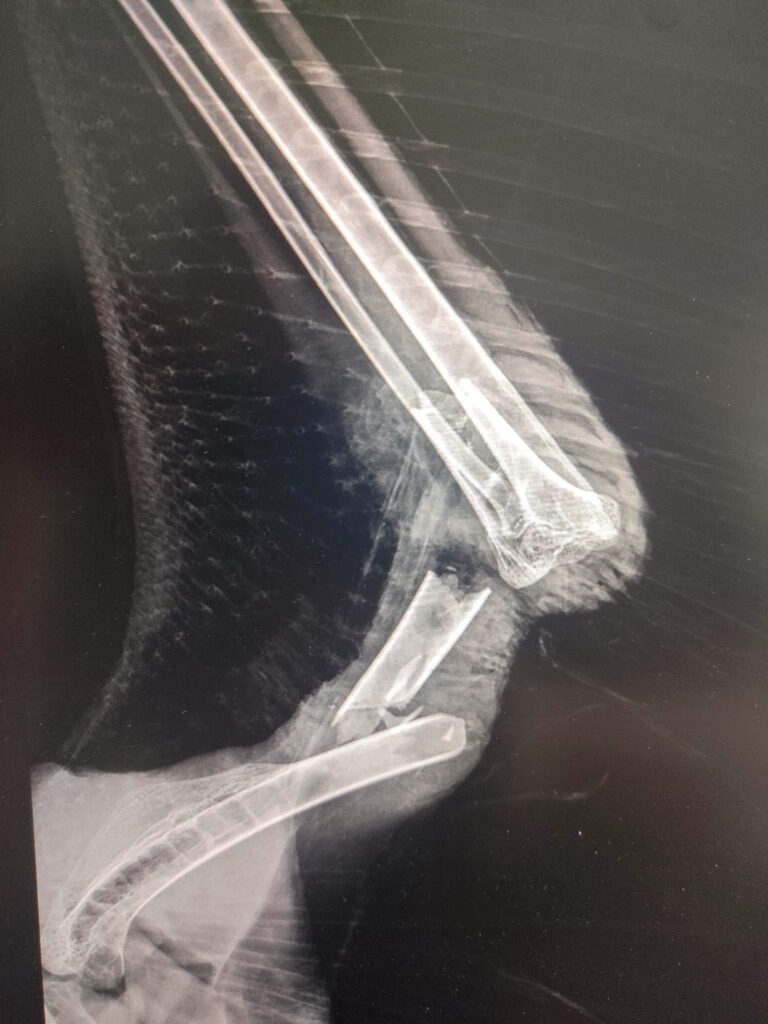

– 13 lutego do Leśnego Ośrodka Rehabilitacji Zwierząt Nadleśnictwa Piotrków, Straż Leśna z Nadleśnictwa Piotrków, przywiozła rannego bielika. Ptaka zauważył myśliwy z Koła Łowieckiego „Tur”na terenie Leśnictwa Straszów. Bielik miał krwawiąca ranę lewego skrzydła. Po badaniach przeprowadzonych przez ośrodkowego lekarza weterynarii okazało się, że jest złamana kość ramieniowa. Rana ma charakter ugryzienia i to ono spowodowało, że kość pękła, w dwóch miejscach. Z przeprowadzonych oględzin rany i pomiarów wykonanych na zdjęciach RTG można przypuszczać, że mógł być to duży pies lub wilk! – relacjonuje Paweł Kowalski z Osady Leśnej w Kole.

– Przypuszczamy, że doszło do kłótni pomiędzy drapieżnikami podczas biesiady na jakimś martwym zwierzęciu. Możliwe, że ptak chciał się przyłączyć do posiłku i został ugryziony. Niestety, mimo konsultacji z wieloma specjalistami chirurgi weterynaryjnej, skrzydła nie udało się uratować. „Walenty” bo takie otrzymał imię, jest już po zabiegu i szybko nabiera sił. Jak na razie rana goi się bardzo dobrze. Wielka szkoda bo jest to dorosły ptak i powinien już przystępować do okresu lęgowego – dodaje leśnik.